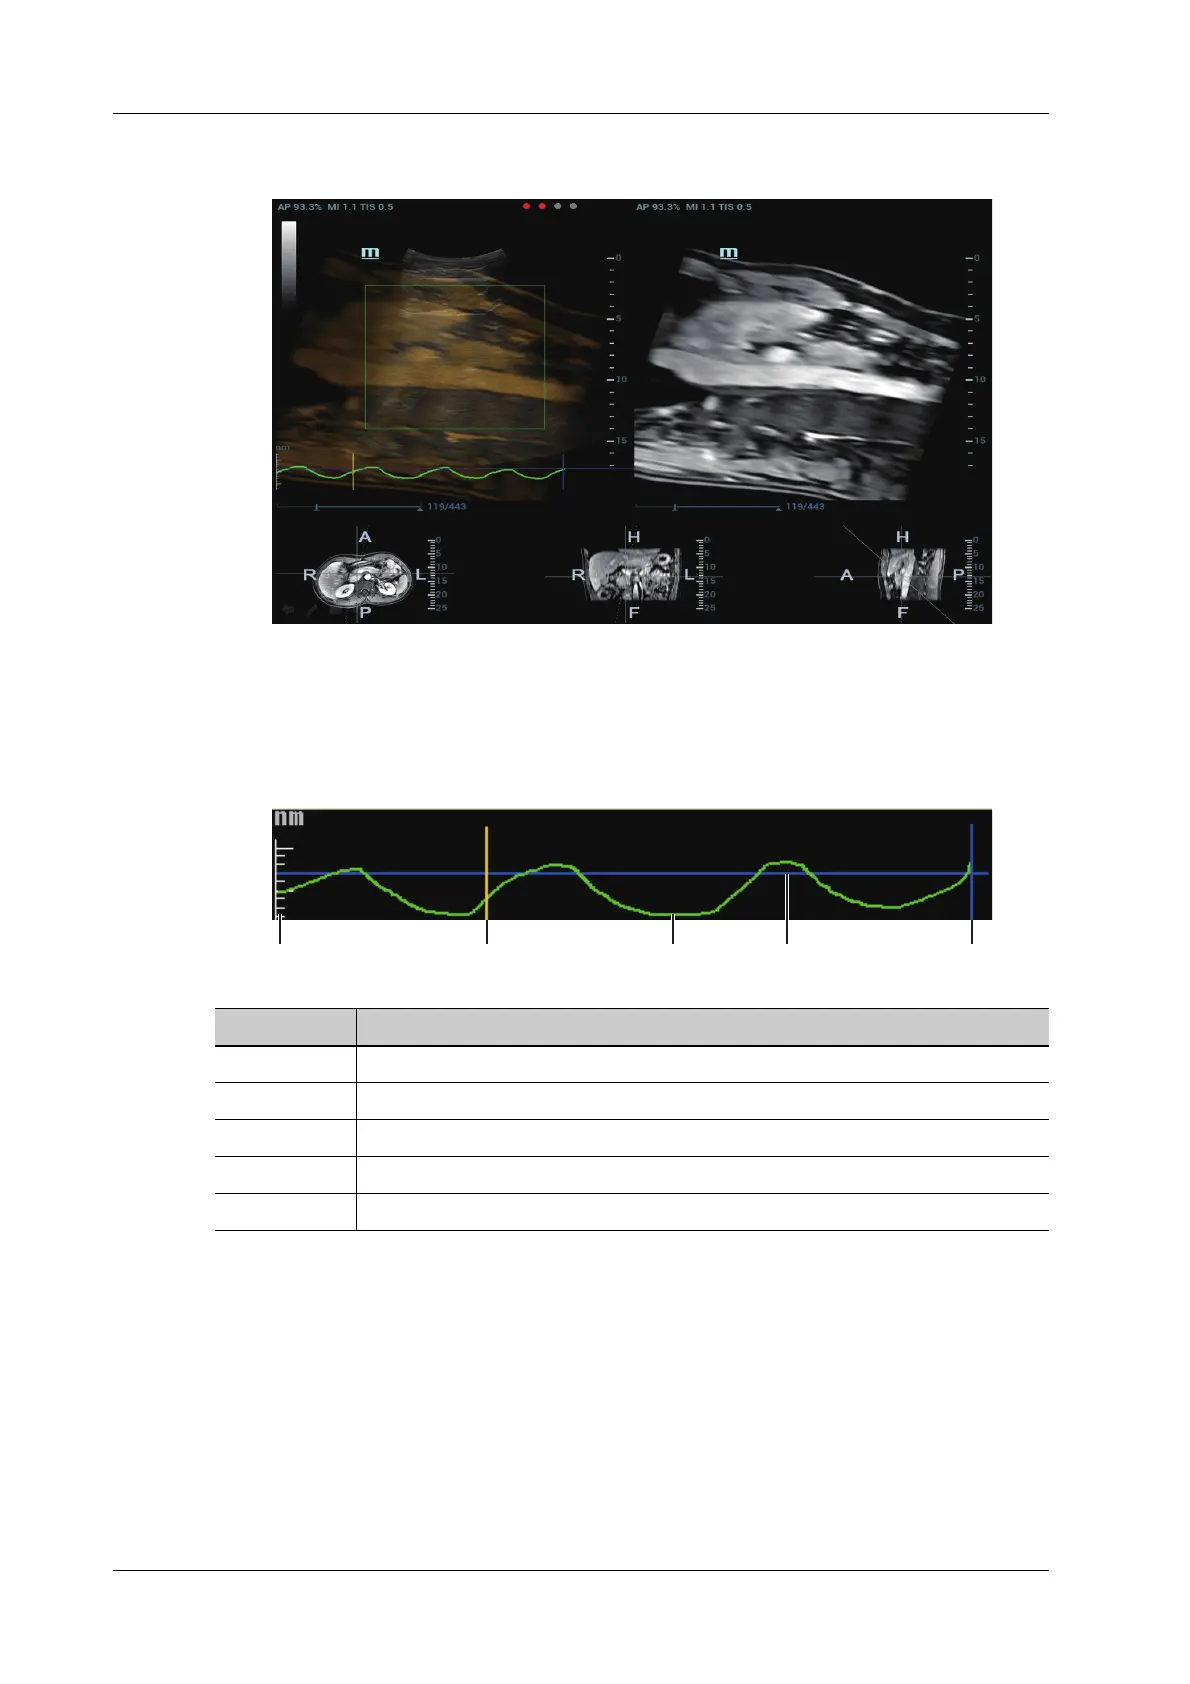

bar appears on the screen. The ultrasound cine plays automatically after the capturing is

finished.

The Ultrasound System selects one premium phase of respiration curve automatically after

the capturing is finished. It is prepared for the motion modeling. You can set the start frame

and end frame to select one phase of the respiration curve.

Respiration Curve Description:

1. Respiration Curve Scale (respiration depth).

2. Set Modeling start (start point of motion modeling of the respiration curve).

3. The green curve is the respiration depth in real-time respiration.

4. The blue curve is the respiration depth at last registration.

5. Set Modeling End (end point of motion modeling of the respiration curve).

12345